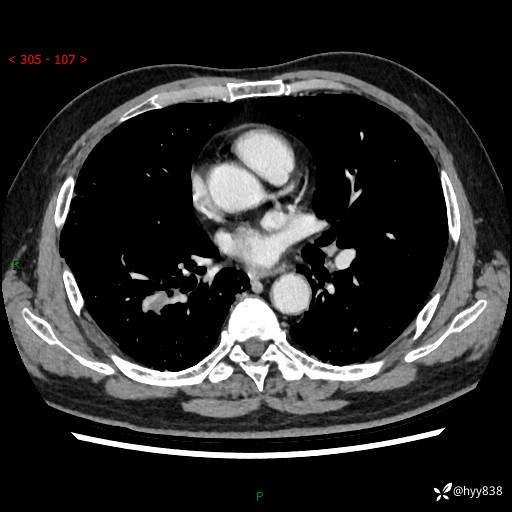

71岁/男,咳嗽伴气促半月。一年前肺手术史,又见两个结节,穿刺结果意外---结果公布~

【现病史】:患者半月前无明显诱因出现咳嗽、咳痰,为白色粘痰,无明显加重与缓解因素,伴气促,无发热,无大量脓痰,无胸痛、咯血,无哮鸣音,到我院就诊,胸部CT示右肺结节增大,并口服药物治疗无明显好转,具体用药不详,为求进一步治疗随来我院,经门诊以“孤立性肺结节”收入我科。 病程中患者精神、饮食可,睡眠不佳,大小便正常,体力下降,体重未见明显下降。

[既往史]:2022-06于当地第一人民医院确诊慢阻肺,现规律使用杰润(1次/日);2023-04-06于当地市第一人民医院行胸腔镜右肺上叶楔形切除术+右肺上叶切除术+淋巴结清扫术+胸膜黏连松解术,确诊为右肺鳞癌 pT2aN0M0 Ib期

【检查】:胸部CT平扫+增强